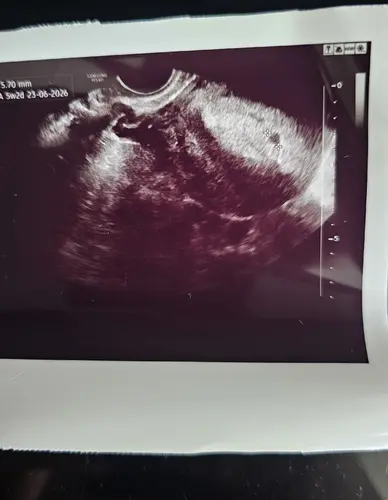

zo zag het er bij mij uit met 4 weken vorige week. vandaag echt al wat meer gezien! met 5 weken. kan het niet zijn dat je toch 4 weken bent schat?